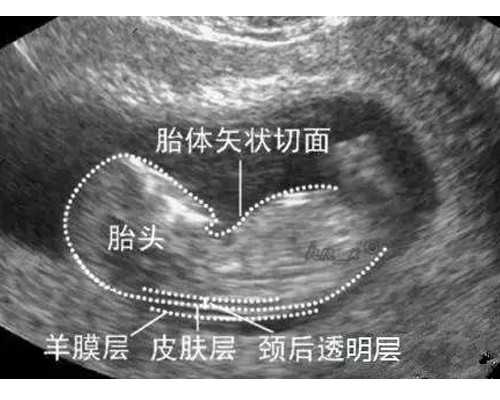

香港DNA验血检测,只需从少数怀孕母亲的手臂取静脉血,在检测中提取胎儿的DNA进行检测,首要经过两次高速离心,运用该试剂从中提取DNA将上清液染色并调查。假如有Y染色体,则意味着腹部的婴儿是男性宝宝,假如不是女人宝宝,则能够在24小时内知道成果。在香港进行性行为测验的条件1,需求B超查看承认胎龄7周以上;2,一年内没有男宝,六个月没有男轮胎;3.半年内未进行大器官移植手术或输血。满意上述条件,测验的精确率可到达99.5%,香港测验dna测验性别是迄今为止最精确,最安全,最便利的办法。怎么承认契合条件的孕龄香港DNA验血检测?